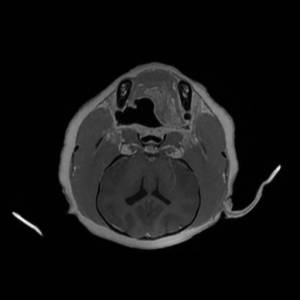

Main Gallery

Playing with a photo gallery function. It is possible to have multiple galleries, each within a namespace.